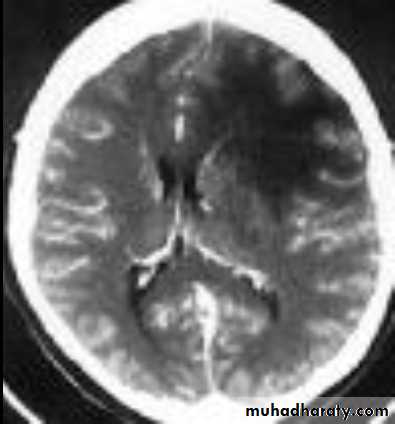

• Computed Tomography scan (CT scan) with/without contrast• Magnetic Resonance Imaging (MRI) with/without contrast